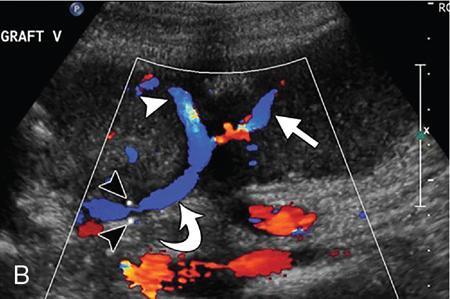

Kajal Patel, L. Murali Krishna Pancreatic transplantation is currently the only effective treatment for type 1 diabetes mellitus (93% of cases) allowing long-term glycaemic control without exogenous insulin injections. Additionally, it also counteracts the complications of diabetes mellitus, including diabetic neuropathy, retinopathy, vasculopathy and end-stage renal failure. The standard procedure is transplantation of a whole-organ cadaveric pancreas but less-invasive approaches such as islet cell transplantation are in development. Simultaneous pancreas–kidney (SPK) transplantation (78%) is done in most of the cases with same donor. In 16% cases, pancreas transplant can be done after kidney transplant also. But rarely, isolated pancreatic transplant (6%) can be done. The first pancreatic transplantation was performed in 1966 by the team of Dr. Kelly, Dr. Lillehei, Dr. Merkel, Dr. Idezuki Y and Dr. Goetz, 3 years after the first kidney transplantation. According to Scientific Registry of the United Network for Organ Sharing (UNOS) and the International Pancreas Transplant Registry (IPTR), the national 1-year patient, kidney and pancreas survival rates for recipients of an SPK transplant are 95%, 89% and 85%, respectively. Pancreas grafts have vascular and enteric connections that vary in their anatomic approach and understanding of this is critical for imaging. Imaging techniques are directed to display the pancreatic transplant arterial and venous vasculature, parenchyma and intestinal drainage pathway. Various surgical techniques have evolved over the years especially in the recent decade. Imaging of these patients should also be done based in the common surgical techniques and complications that arise of these surgeries. Though multiple modalities like ultrasonography (US), computed tomography (CT) and magnetic resonance (MR) imaging, radionuclide study and digital subtraction angiography (DSA) are available, each of them have their own advantages and limitations and usually a multimodality approach is required to diagnose the spectrum of complications. Preoperative evaluation typically considers the potential recipient’s age and ability to survive the operation. A relative contra-indication is the patient’s age (>55 years), due to the fact that the success rate is superior in younger individuals. Key components of the assessment include determining the presence of renal, cardiac, peripheral vascular, cerebro-vascular and psychiatric diseases. The pretransplant work-up consists of extensive laboratory, infectious and physiologic testing. Chest radiography is required for preoperative fitness of recipient. The extent of aorto-iliac calcification of recipients, a factor in choice of implant site, is evaluated with unenhanced CT. Donor factors such as age, sex, body mass index, cause of death, donation after cardiac death, serum creatinine and preservation time (cold ischaemia) can influence the outcome of pancreas transplantation. Usually, evaluation of donor pancreas is best done by the pancreatic transplant surgeon intraoperatively. Visual inspection of pancreas in terms of its size, texture, colour, fibrosis, fatty infiltration and its vascular supply is essential. There is very little role for preoperative imaging in the setting of deceased organ donation. The donor’s pancreas is harvested en bloc with its respective vascular support and a variable duodenal segment that contains the ampulla of Vater. The most common technique consists placing the pancreatic graft intraperitoneally in the right pelvic region with the duodenal segment facing cephalad and the renal graft in the left iliac fossa, extraperitoneally. Whole pancreatic graft transplantation can be performed with a duodenal segment; in this type of transplantation, donor’s duodenum is anastomosed with the recipient’s small bowel loop for enteric exocrine drainage and grafted portal vein is anastomosed with common iliac vein or inferior vena cava for systemic endocrine drainage (Fig. 9.20.1). Another way of restoring the endocrine drainage, grafted portal vein may be anastomosed with the recipient’s portal venous system and for exocrine drainage duodenal segment may be anastomosed with the urinary bladder. Duodenoenterostomy done by side to side anastomosis of donor’s duodenal segment to the recipient’s small bowel loop. Arterial supply is established by using the donor’s aortic patch, containing the splenic artery and the superior mesenteric artery (SMA), which is anastomosed to the recipient’s common or external iliac artery. Native pancreas of patient is left untouched in the upper abdomen. After placement of pancreatic graft by surgeon, pancreatic graft Doppler evaluation should be done intraoperatively. Intraoperative ultrasound probe is directly put on anastomotic artery and vein which show normal colour flow without evidence of thrombosis. In the case of occlusion, there is no evidence of colour flow. In the case of occlusion, surgeon does re-anastomosis of vessels once thrombi are removed. Due to its superficial location in pelvis and visualization of pulsation of vessels, visual inspection is sufficient for patency of vessels. So most of the time intra-operative Doppler study is not necessary. Postoperative imaging of pancreas transplantation is a challenge for the radiologist because of the altered surgical anatomy, identifying the pancreatic graft from adjacent structures and various postoperative complications that may arise posttransplantation. Imaging evaluation of the pancreas transplant grafts is commonly performed by a multitechnique approach. The most commonly utilized scanning techniques include US, CT and MR imaging. DSA and radionuclide study are routinely not performed nowadays. Ultrasound usually represents the first line imaging method in the assessment of the pancreatic graft, due to its portability, repeatability for ill and unstable patients in the immediate postoperative period, lack of ionizing radiation, and it provides a real-time vascular flow map which may allow detection of vascular anastomotic stenosis and reduced pancreatic graft perfusion. Its evaluation may, however, be limited due to the intraperitoneal position of the pancreas graft, in particular with the portal enteric approach with the organ in the right upper abdomen and intestinal gas overlap. Unless abnormally dilated, the duodenal component often cannot be separately evaluated by ultrasound. Additionally, ultrasound may be fundamental in guiding the percutaneous biopsy. Although the lack of an organ capsule generally results in an ill-defined appearance, the pancreatic transplant can be identified by its relatively cylindrical shape. In greyscale B-mode, the normal pancreatic graft presents homogeneous echotexture, lower than the native pancreas and the surrounding mesenteric or epiploic fatty tissue (Fig. 9.20.2). Colour and power Doppler US play a vital role in demonstrating pancreas transplant perfusion and vascular anatomy. We would also be able to visualize the Y arterial graft, graft vein, splenic artery and vein (Fig. 9.20.3A and B). Venous structures demonstrate a monophasic waveform within an anechoic lumen and velocities ranging between 10 and 60 cm/s. Normal arterial waveform exhibits a sharp systolic upstroke and a continuous diastolic flow. In the immediate postoperative period, the velocities of the arterial anastomosis may be very high as 400 cm/s due to possible postoperative oedema and/or due to kinking of the anastomosis. Usually in both the cases, the arterial anastomotic velocities gradually decrease on in follow-up. The resistive index (RI) may be of limited use to diagnose graft rejection, as the values may be as high as 0.9 and are variable throughout the gland. Due to the presence of renal capsule in a transplanted kidney, there is elevated vascular resistance when there is intrarenal oedema; however, due to the absence of capsule in the transplanted pancreas, the vascular resistance will be normal in spite of oedema secondary to pancreatitis or rejection. CT is generally required after an abnormal ultrasound or whenever the patient presents unexplained fever, abdominal pain or when abnormal laboratory data are found. Contrast-enhanced CT helps to evaluate the graft parenchyma, the enteric and vascular anastomosis and in diagnosing postoperative complications such as focal collections, vascular thrombosis or pneumoperitoneum. In noncontrast CT scan, pancreatic graft appears as a homogeneous isodense soft tissue organ. It is more difficult to differentiate between pancreatic graft and nonopacified and nondistended small bowel loop in plain/noncontrast CT scan. But you can always make out the surgical clips which are stapled on duodenal stump, which can be helpful for localization of pancreatic graft. Nonenhanced images should be acquired with the goal of locating the graft and possible early thrombus or haematoma. The protocol used should include (positive) enteric contrast that allows identification of intestinal loops adjacent to the graft and distinction from possible liquid collections (Fig. 9.20.4A). The donor’s duodenum is frequently collapsed and may fill (or not) with the given oral contrast. IV contrast material is administered infrequently, to avoid the risk of nephrotoxicity, if native renal function is impaired. About 120–150 mL of contrast medium greater than 350 mg iodine per millilitre is injected at the rate of 4–6 mL/s. Late arterial phase can be obtained with the bolus-tracking technique located in the common iliac artery (attenuation value of 150 HU) and is very useful in the assessment of parenchymal enhancement and arterial anastomosis; 50 seconds after the administration of intravenous contrast material, the portal venous phase evaluates the respective drainage and possible associated venous complications (Fig. 9.20.4B). CT images are evaluated by axial, multiplanar reformats and three-dimensional maximum intensity projection (MIP) and volume-rendered techniques. The normal pancreatic parenchyma will enhance uniformly more in the arterial phase than in the venous phase. The iliac arterial graft, peripancreatic and intrapancreatic arterial vasculature, as well as the anastomosis of the donor portal vein to the recipient iliac or superior mesenteric vein, should be delineated. Coronal reformats are the best to illustrate the intestinal anastomosis and to determine if the graft is placed inferiorly for a systemic venous drainage or superiorly for a portal venous drainage. MR is usually indicated in young patients in which cumulative radiation is an essential consideration. Contrast-enhanced MR angiography is used for evaluating the arterial and venous anatomy of pancreatic graft; however, it is difficult to access the enteric anastomosis and postoperative complications due to low spatial resolution. Also, it is a challenge to image sick patients requiring intense monitoring and those with metallic clips. An appropriate protocol includes axial T1-weighted (T1WI) (precontrast; in-phase and out-of-phase), coronal T2-weighted (T2WI) fast-spin-echo and axial T2-weighted fat-suppressed sequences. Furthermore, images after intravenous contrast administration (gadolinium-based) should be acquired in arterial and venous phases. Unenhanced MR imaging readily helps distinguish the pancreatic allograft from adjacent structures and is superior to CT without intravenous contrast material. In plain MRI of abdomen, pancreatic graft appears hyperintense as compared to liver and appears as homogenous structure on T1-weighted images. Normal pancreatic graft’s signal intensity is between that of fluid and muscle on T2-weighted images. Various pathologic process of graft pancreas is more related to increased glandular water content, so T2-weighted images are more sensitive to diagnose graft pathology (Fig. 9.20.5A). Axial and coronal images are useful in displaying pancreatic and peripancreatic graft oedema, as occurs in pancreatitis, and in characterizing peritransplant fluid collections (haematoma/seroma). The MR angiography helps to access the arterial and venous anatomy and can diagnose arterial or venous stenosis and venous thrombosis. The normal pancreas graft enhances briskly and homogeneously in the late arterial phase (Fig. 9.20.5B). Gadolinium-based contrast agents may pose the risk of nephrogenic systemic fibrosis in selected patients with advanced renal dysfunction. The normal pancreatic duct is generally not visible with US or CT but may be observed as a thin (≤3 mm) smooth line on T2W MRI.